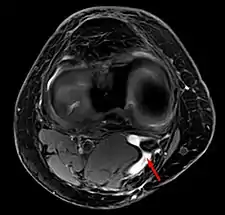

In adults, Baker's cysts usually arise from almost any form of knee arthritis (e.g., rheumatoid arthritis) or cartilage (particularly a meniscus) tear. Baker's cysts in children do not point to underlying joint disease. Baker's cysts arise between the tendons of the medial head of the gastrocnemius and the semimembranosus muscles. They are posterior to the medial femoral condyle.

Diagnosis is by examination. A Baker's cyst is easier to see from behind with the patient standing with knees fully extended. It is most easily palpated (felt) with the knee partially flexed. Diagnosis is confirmed by ultrasonography, although if needed and there is no suspicion of a popliteal artery aneurysm then aspiration of synovial fluid from the cyst may be undertaken with care. An MRI image can reveal presence of a Baker's cyst.